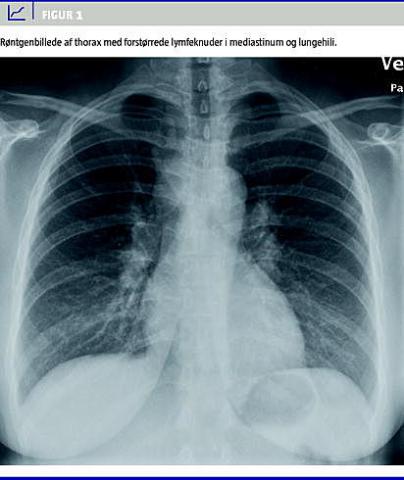

Den endelige diagnose blev stillet ved biopsi af de patologisk forstørrede lymfeknuder i mediastinum og lungehilii, der var påvist ved røntgen og computertomografi af thorax (Figur 1 ).